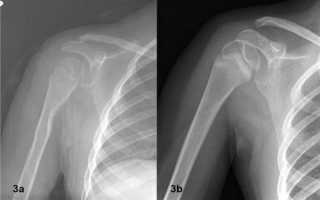

Рентген плечевого сустава в двух проекциях (прямой и боковой снимок) показывает довольно подробную картину патологических изменений. Кроме состояния самого сочленения, с его помощью можно оценить состояние ключицы и лопатки. Благодаря прямой проекции врач определяет степень смещения переломов (если таковые есть), на боковых снимках (аксиальных) хорошо видны изменения краев вертлужной впадины.

- Передний вывих плеча – наиболее распространенное структурное нарушение, встречается в 98 % случаев.

- Задние вывихи диагностируются редко

- Вывих с переломом шейки плечевой кости.

- Застарелый вывих. Такие патологии тяжело поддаются терапии. на мягких тканях образуются рубцы, меняется тонус мышц, развивается дегенеративный процесс мышечной ткани.

При диагностике проблемы с плечевым суставом часто достаточно просто расспросить пациента, осмотреть его. В более тяжелых случаях, когда просматривается стойкое нарушение функциональности сустава, проводится рентгенографическое исследование. Снимок делается в прямой проекции. С помощью рентгена оцениваются размеры, форма сустава. Данная проверка помогает диагностировать артрит в плече, обыкновенный вывих.